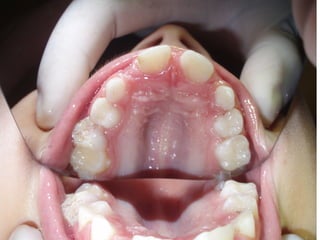

Πρώτη σχολική ηλικία 6-10 ετών

   Αρχίζει αλλαγή των τομέων και η ανατολή των

πρώτων μόνιμων γομφίων (μεικτή οδοντοφυΐα)

   Παρατηρούμε η αλλαγή δοντιών να γίνεται με τη

σωστή σειρά και στη σωστή θέση

   Μπορεί να χρειαστεί πρώιμη ορθοδοντική

θεραπεία, για να αποφευχθούν πιο δύσκολες και

πολύπλοκες εργασίες αργότερα

   Διατήρηση νεογιλών δοντιών στον οδοντικό

φραγμό μέχρι τη φυσιολογική τους απόπτωση

Προληπτικά μέτρα - Καλύψεις οπών και

σχισμών (ΚΟΣ)

   Οι μασητικές επιφάνειες των οπισθίων δοντιών

ευνοούν την κατακράτηση τροφών και μικροβίων και

συχνά τερηδονίζονται αμέσως μετά την ανατολή τους.